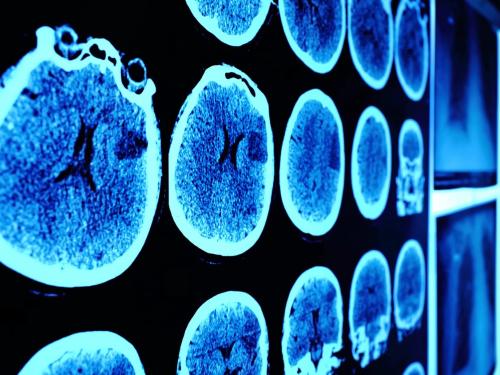

CT (computerised tomography) scan

A CT scan takes a series of x-rays, which build up a three-dimensional picture of the inside of the body. It takes 10–30 minutes and is painless, but your child may be given a sedative or general anaesthetic to make sure they lie still. Sometimes, special dyes are injected into a vein to make certain parts of the body show up better on the CT scan.